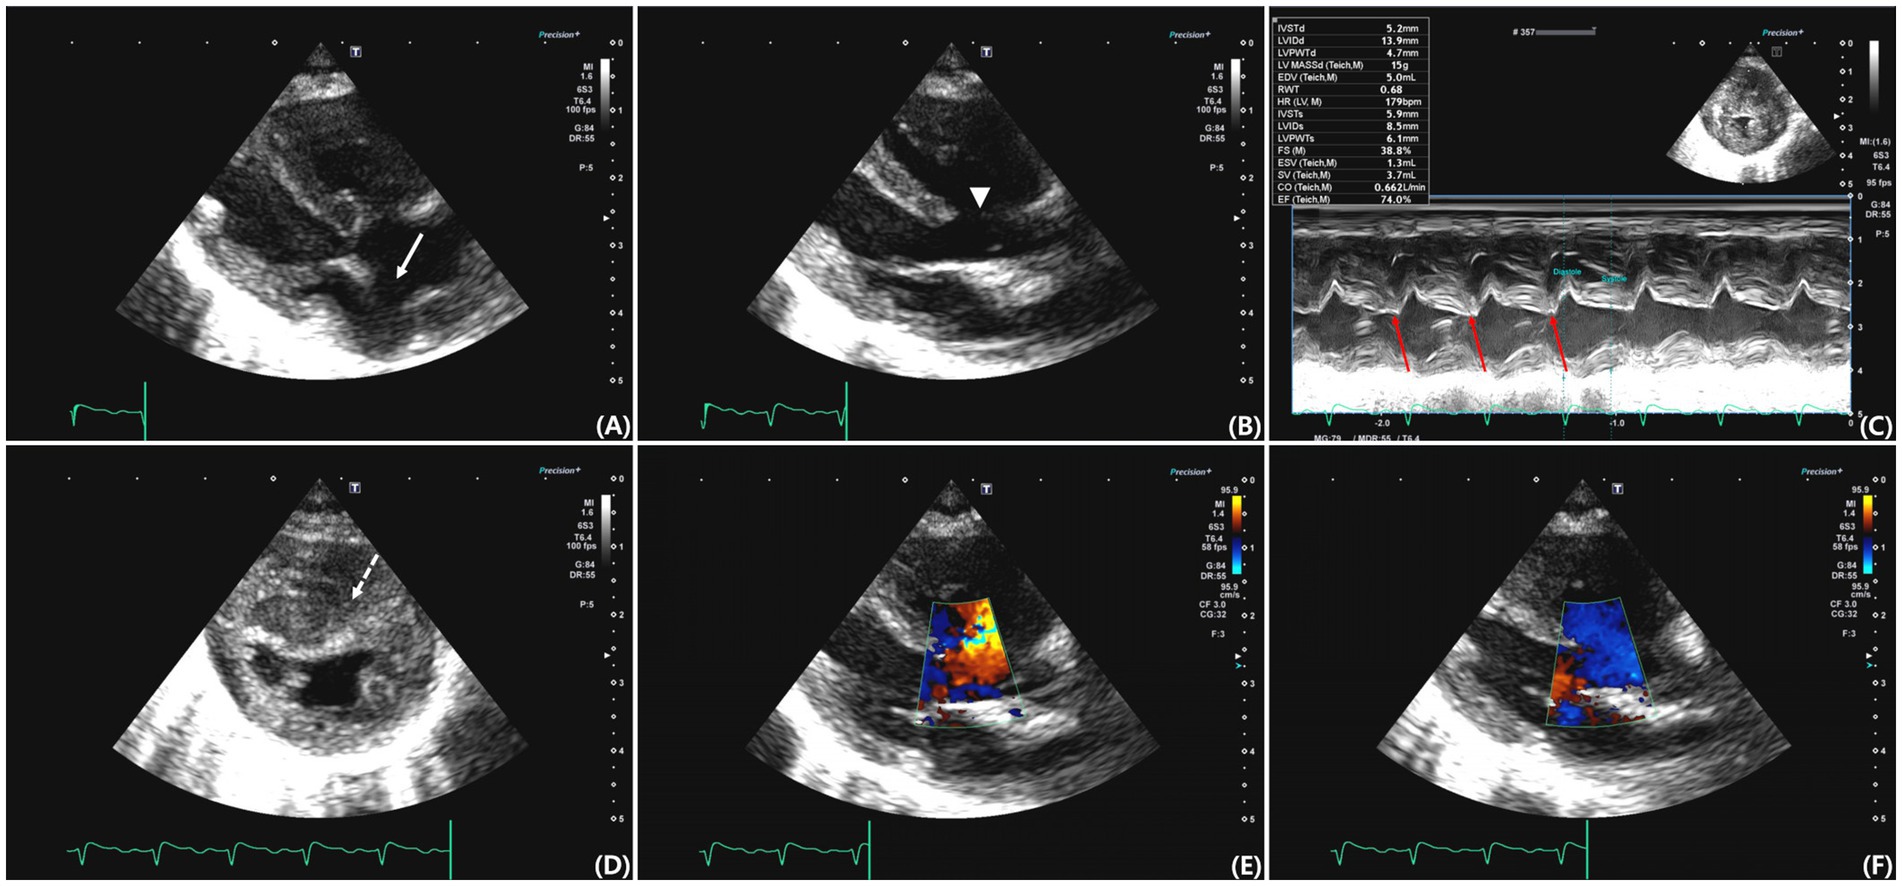

Concurrent atrial septal defect (ASD) and ventricular septal defect (VSD) are rare in cats. A 7-month-old intact female Sphynx cat was presented for evaluation of respiratory distress and exercise intolerance. Thoracic radiographs showed generalized cardiomegaly and pulmonary infiltrates, consistent with cardiogenic pulmonary edema. Transthoracic echocardiography revealed an ostium secundum–type ASD and a perimembranous VSD, with structurally normal atrioventricular valves and annuli. These features supported the diagnosis of concurrent ASD and VSD, rather than an atrioventricular septal defect. Color Doppler echocardiography and agitated saline contrast studies confirmed bidirectional shunting at both defect sites. Additionally, echocardiographic findings were consistent with pulmonary hypertension. As Eisenmenger syndrome was suspected and the owner declined invasive intervention, surgical repair was not performed. Initial treatment with furosemide and supplemental oxygen led to clinical improvement. The owner later discontinued diuretics; however, the cat remained asymptomatic for several months. Cyanosis and erythrocytosis developed approximately 8 months after initial presentation. Follow-up thoracic imaging and Doppler echocardiography demonstrated reduced cardiac silhouette size without recurrent pulmonary edema, right-sided chamber enlargement with right ventricular hypertrophy, and decreased pulmonary-to-systemic flow ratio, consistent with progression of Eisenmenger physiology. Medical management with phlebotomy, sildenafil, clopidogrel, and oxygen supplementation provided temporary stabilization; however, the cat eventually died approximately 1 year after diagnosis, likely due to disease progression and inconsistent therapeutic compliance. Postmortem examination confirmed both septal defects and marked right ventricular hypertrophy, consistent with the ante-mortem imaging findings. Histopathological examination revealed pulmonary vascular remodeling and myocardial fibrosis, indicative of chronic pulmonary hypertension. This report represents the first documented case of concurrent ASD and VSD with Eisenmenger physiology in a cat, with long-term clinical follow-up and postmortem confirmation.